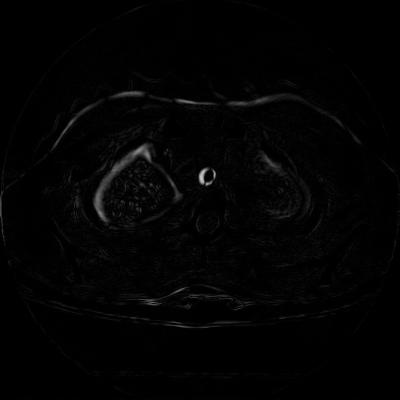

We now consider applying the proposed image registration method on real lung CT images retrieved from the National Lung Screening Trial (NLST) dataset [1]. Fig. 9(a) and Fig. 9(b) show two slices of lung CT images that we use as the source and the target (see Fig. 9(c) for the absolute intensity difference). We remark that the CT images are originally with different intensity, and so we apply an intensity histogram matching before running the registration experiment. Fig. 9(d) shows the registration result obtained by our proposed method. It can be observed that our method successfully produces a large deformation on the right lung of the source image to match that of the target image (see also Fig. 9(e) for the final absolute intensity difference). On the contrary, DDemons [47] (Fig. 9(f)), LDDMM [5] (Fig. 9(g)), Elastix [29] (Fig. 9(h)) and DROP [18] (Fig. 9(i)) all fail to produce an accurate and bijective registration result. This shows that our method is more capable of handling large deformation image registration.

We then test our method on slices of chest CT images obtained from the Open Access Biomedical Image Search Engine [2]. Fig. 10(a) and 10(b) show the source image and target image respectively, and the intensity difference is shown in Fig. 10(c). The registration result obtained by our proposed method is shown in Fig. 10(d) (see also the result with the deformed underlying grid in Fig. 10(e)). From the final intensity difference plot in Fig. 10(f), it is easily to see that our method matches not only the two large components but also the small dot at the center very well. On the contrary, DDemons [47] produces a suboptimal registration result with a significantly larger mismatch of the small component at the center (see Fig. 10(g) and Fig. 10(h)).